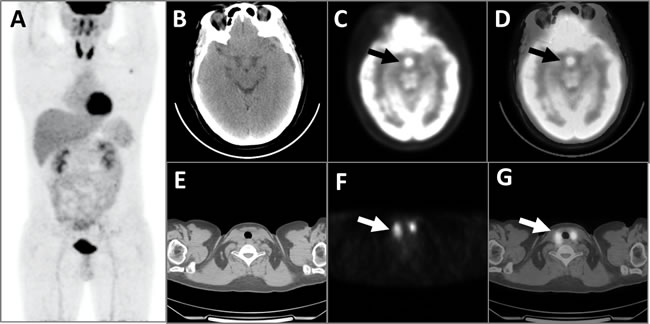

The three patients with LCH had an SUVmax ranged from 6.0 to 26.0 (15.0 ± 10.2). In addition to pituitary hypermetabolism, one patient had concurrent diffuse thyroid hypermetabolism, with a postoperative residual thyroid SUVmax of 11.3 (Figure 1). The second patient was found multiple hypermetabolic lymph nodes in the bilateral submandibular regions, neck, armpits, abdomen, retroperitoneum, pelvis, and bilateral groins, with SUVmax ranged from 2.0 to 13.2 (Figure 2). In addition to multiple hypermetabolic lymph nodes in or around the neck, hilar and mediastinum, retroperitoneum, iliac vessels, and groin (SUVmax = 15.6~18.9), the third patient also had concurrent thyroid hypermetabolism (SUVmax = 7.7), spleen enlargement and hypermetabolism (SUVmax = 8.0), local bone destruction and hypermetabolism (SUVmax = 8.7) around the left iliac wing and left pubis [1]. All the three patients had a definitive diagnosis established via a pathological examination based on other tissues’ biopsy other than pituitary.

Figure 1: This patient with LCH had concurrent diffuse thyroid hypermetabolism. The MIP image of the PET A. showed diffuse abnormal FDG hypermetabolism with an SUVmax of 11.3 in the residual bilateral thyroid, which was consistent with the CT scanning E., PET cross-section images F., and fusion images G. of the thyroid (white arrows). PET images of the brain B. showed significantly elevated FDG metabolic activity with an SUVmax of 12.9 (black arrows) in the pituitary, which was confirmed by the corresponding CT C. and fusion D. images.